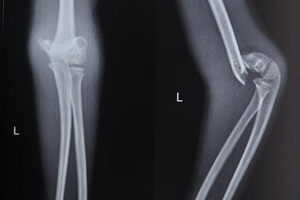

Trauma-Fractures in children

As parents, we know an active child is a happy child, but this can sometimes lead to bone injuries. According to Dr. Rohit Jain, a leading sports injury specialist and pediatric orthopedic doctor, fractures are common, especially in children who engage in sports or rough play.

Types of Fractures:

• Greenstick Fractures : Partial breaks that bend rather than completely shatter.

• Compound Fractures : Bones that break through the skin, requiring immediate care.

• Transverse Fractures : Horizontal breaks often from direct impact.

• Comminuted Fractures : Bones shatter into several pieces, typically from high-impact activities.

• Stress Fractures : Small cracks due to repetitive stress, common in athletes.

Effective Treatment Options

For minor fractures, we use advanced non-surgical methods and specialized plasters to aid healing. In more severe cases, Dr. Jain may recommend surgery for better recovery. Don’t let a fracture hinder your child’s active lifestyle! Contact us today.